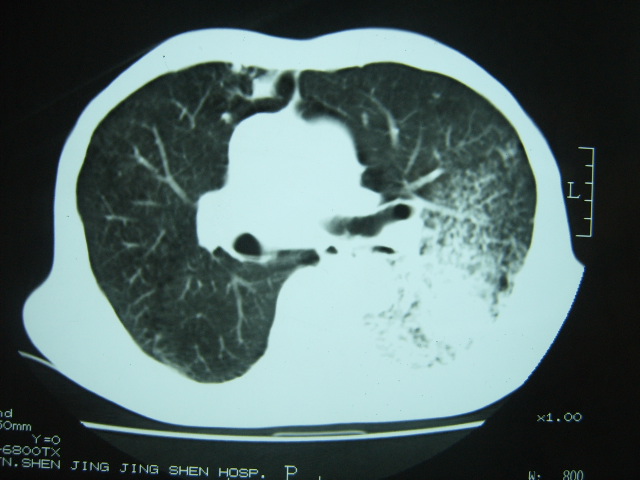

男74岁,咳嗽,寒战,低烧。有糖尿病史。

两肺慢性炎症伴脓肿形成,不除外继发霉菌感染。

1、左下肺肺脓肿,合并霉菌球形成?.2、双肺陈旧性病灶.3、右上肺病灶警惕瘢痕癌,建议定期复查.

两肺结核,左下肺空洞性病变,结核性?炎性?癌性?抗炎治疗后复查。

两肺结核,左下肺大片实变,内见空洞性病变,壁不规则,结合糖尿病史,考虑:结核性?霉菌性?建议结合实验室检查或治疗后复查。